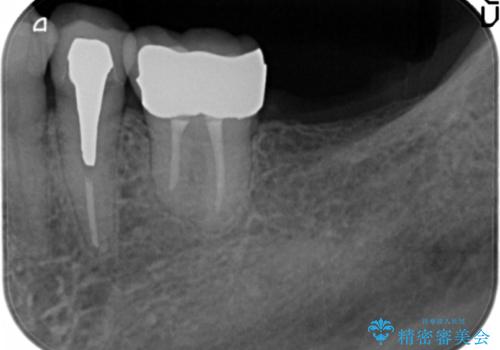

親知らずの移植 4年半経過症例 70代女性

- 親知らずの移植治療から4年半経過した患者様です。

移植した親知らずは全く問題ないそうで、「まるで自分の歯のようです。本当にすごい技術ですね。」とおっしゃって下さいました。

歯肉の腫脹や退縮、動揺も認められませんでした。

自家歯牙移植は40歳以上の場合、若年者に比べ成功率が低くなるとの報告もありますが、状態によっては移植が可能な場合もあります。